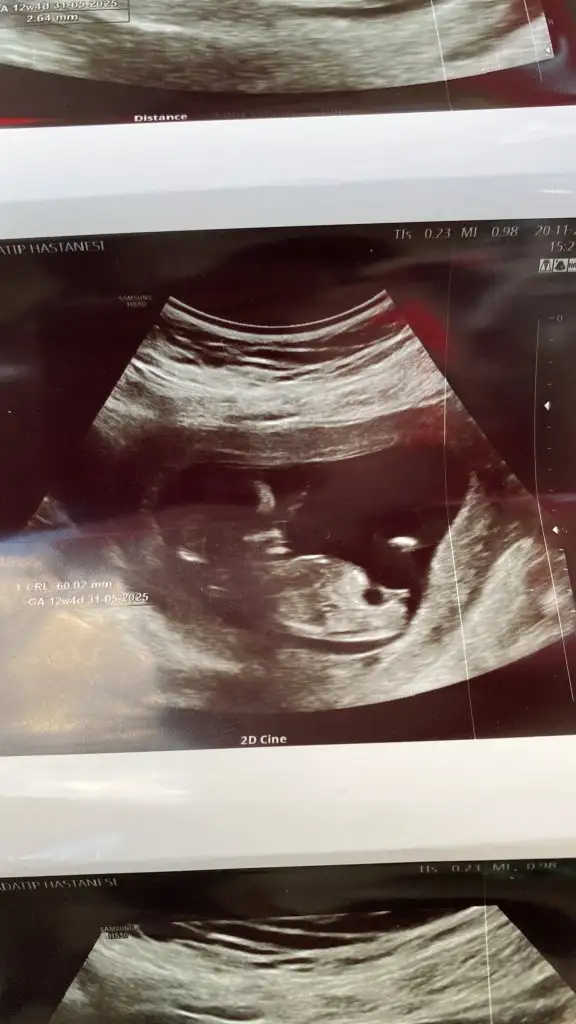

kızlar son kez cinsiyet tahminiiii

Canım belli oldu mu sizin cinsiyet

Belli değil canım ya haftaya net söyleyeceğim dedi doktorum ☺️ Yeni ultrasonlar var ama atayım bakalım yeni tahminler ne olacak ♥️

• fc241d90-2fff-4e98-b643-b49dcb6fdcd7.webp

fc241d90-2fff-4e98-b643-b49dcb6fdcd7.webp

28,5 KB · Görüntüleme: 60

• 44c470ec-61a8-4604-8095-9802a9913f35.webp

44c470ec-61a8-4604-8095-9802a9913f35.webp

27,8 KB · Görüntüleme: 56